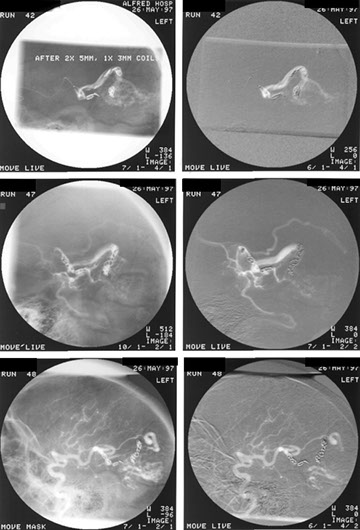

Lady with transient ischaemic attacks. Note the rounded density lateral to the right breast.

Which in the lateral projection can be clearly seen projected over the heart.

This turned out to be another AV malformation which was occluded by multiple coils. Note the post embolisation picture in the bottom right corner.